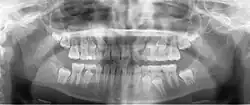

A panoramic radiograph is a panoramic scanning dental X-ray of the upper and lower jaw. It shows a two-dimensional view of a half-circle from ear to ear. Panoramic radiography is a form of focal plane tomography; thus, images of multiple planes are taken to make up the composite panoramic image, where the maxilla and mandible are in the focal trough and the structures that are superficial and deep to the trough are blurred.

Orthopantomograms (OPTs) are used by health care professionals to provide information on: